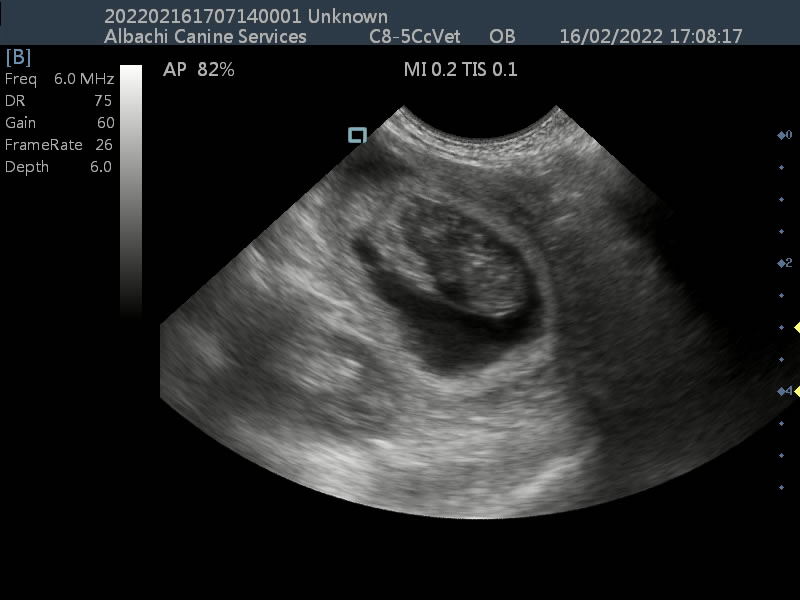

First scan to confirm pregnancy. Very young dog which arrived with its new owner already pregnant so we are monitoring her progress with weekly scanning.

Late Stage Scan Showing Heart and Organ Development

A late stage scan for Elsie the Pomeranian, showing development of pups. Videos and images show developed organs and heart beats.